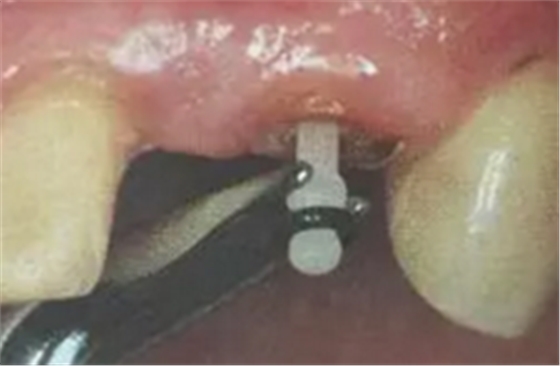

(超聲去除根管殘留物)

通常此時(shí)以超聲潔牙機(jī)更換較細(xì)工作尖進(jìn)入根管(根管消毒沖洗液配合清潔工作后面會(huì)提到),徹底去除樁道根管壁上的附著殘留物,效果明顯。再配合X線片、根管顯微鏡輔助檢查清理的情況下更佳。